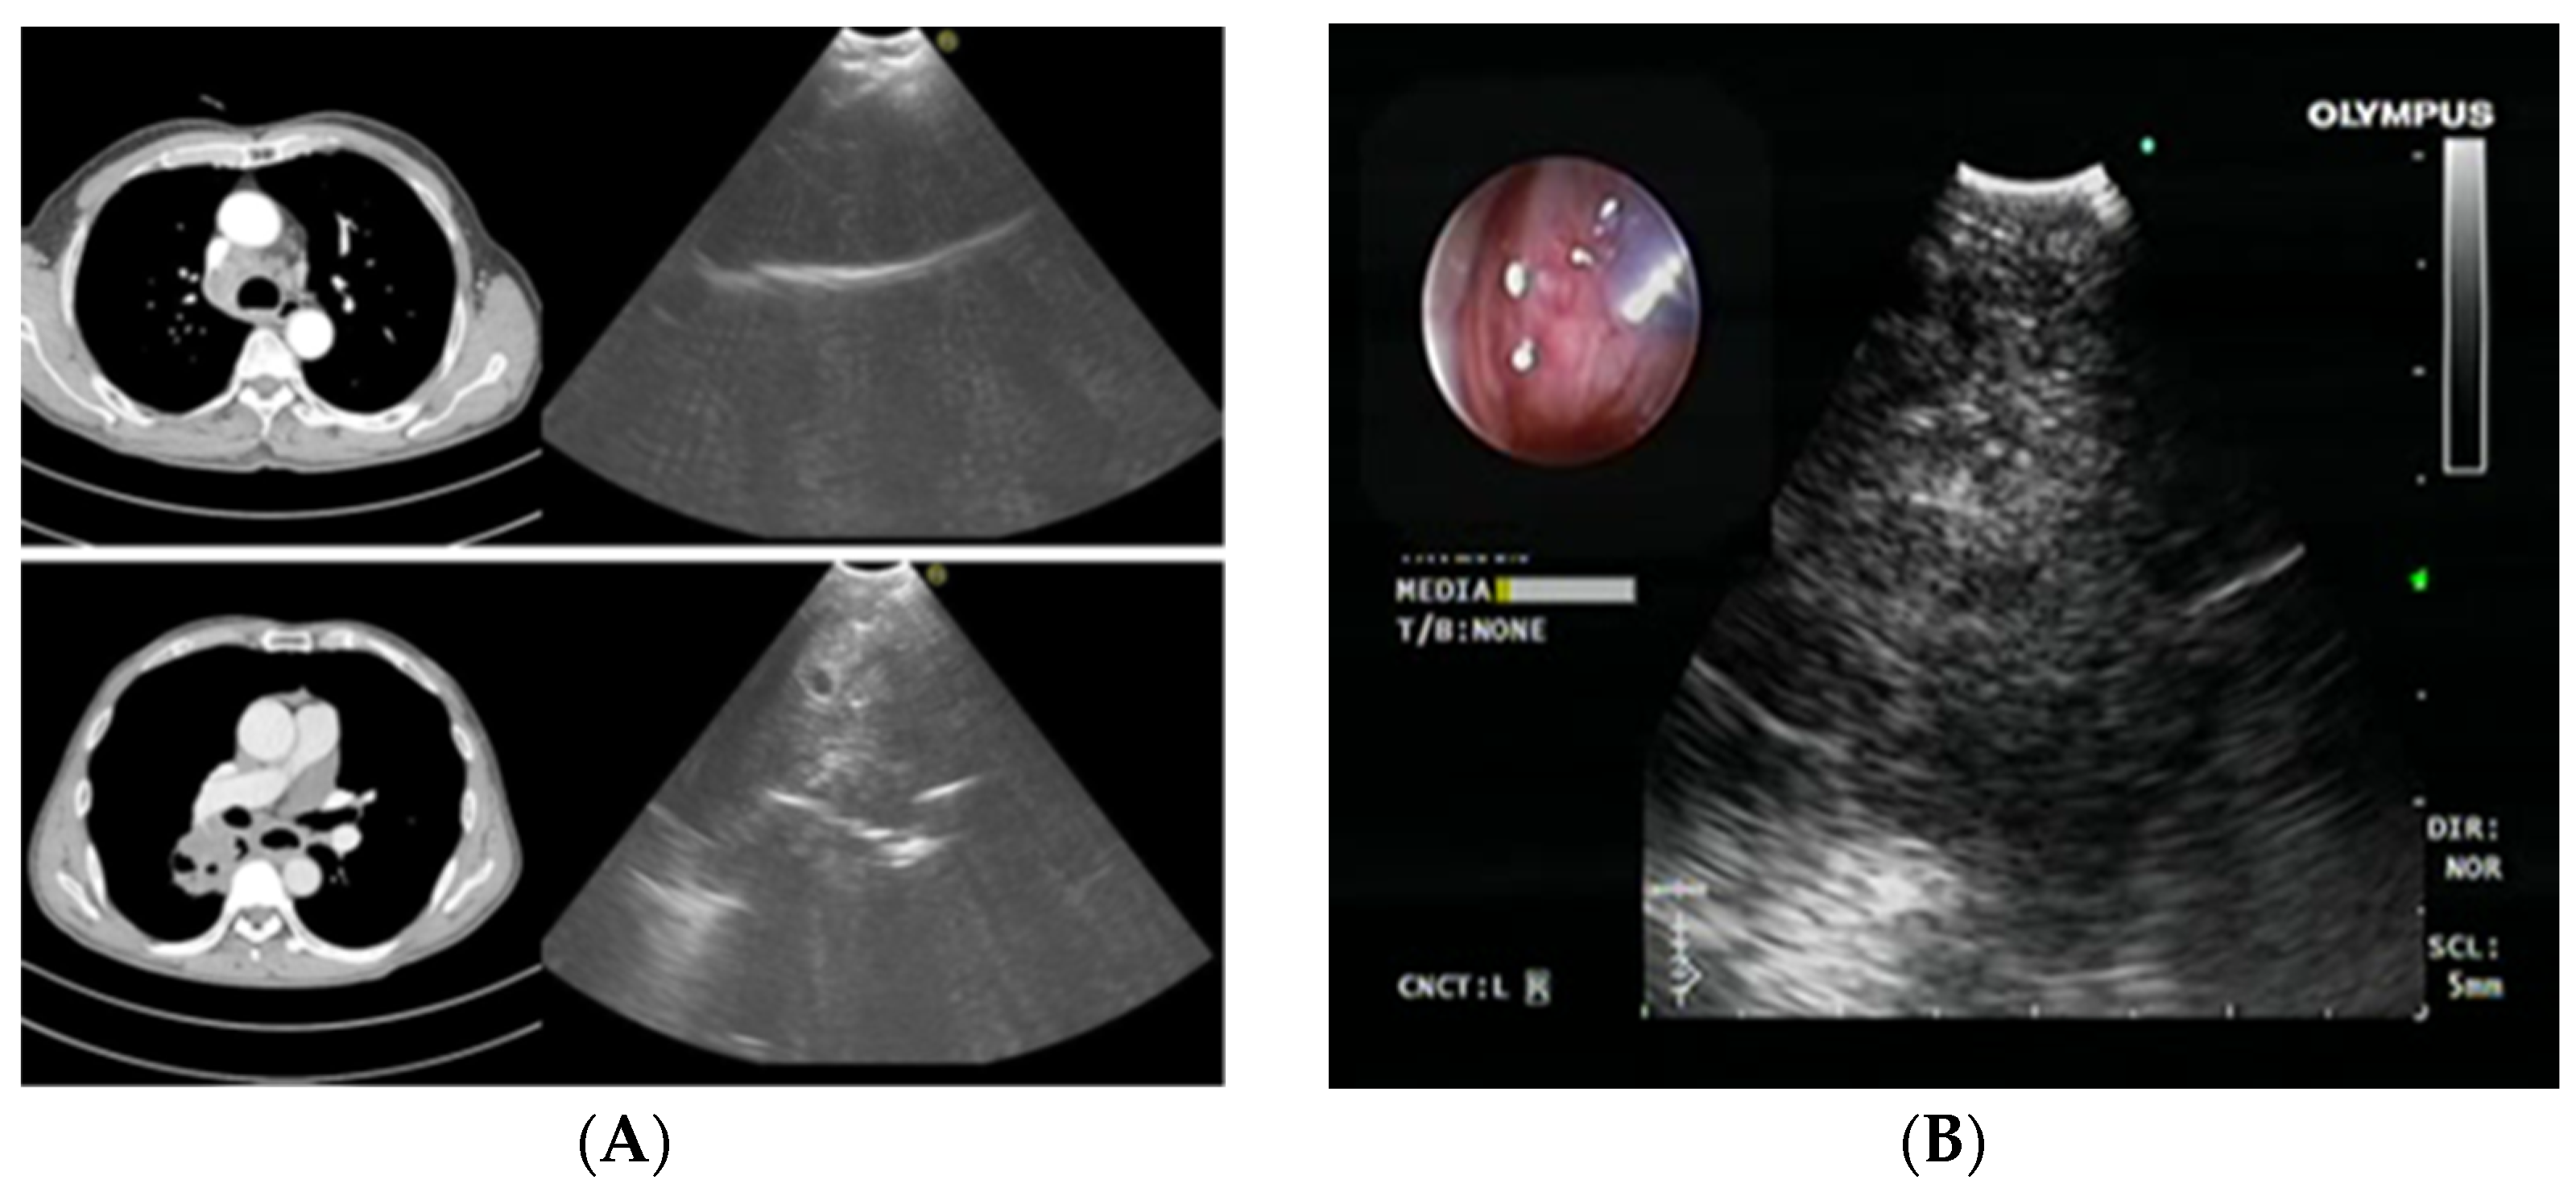

2.2. Radial Probe—Endobronchial Ultrasound with a Guide Sheath in the Diagnosis of Peripheral Lung Lesions

RP-EBUS-GS—Guided Endobronchial Ultrasound in the Era of Molecular Testing of Tumor Tissue